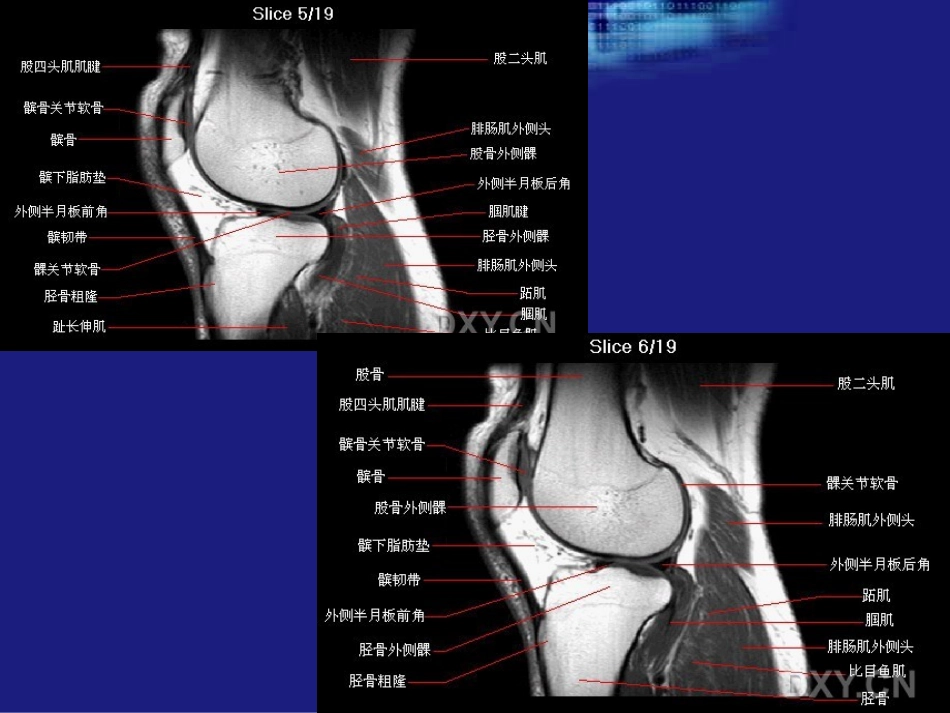

膝关节MRI二、韧带膝关节的韧带较多,以前交叉韧带(ACL),后交叉韧带(PCL),内外侧副韧带等等前交叉韧带起于胫骨上端非关节面髁间隆起前部及外侧半月板前角(外下),向上后外呈扇形,止于股骨外髁内侧面之后部(内上)。后交叉韧带起于胫骨上端非关节面髁间隆起之后部及外侧半月板之后角(内下),向上前内在前交叉韧带之后方,止于股骨内髁外侧面之前部(外上)。后交叉韧带比前交叉韧带大、短、直,更坚强,后部宽大呈扇形。PCL略向后突的弓形。正常MRI的交叉韧带表现为条状低信号结构,界清光滑。图示红色圆形部分是板股韧带----外侧半月板与股骨间的韧带,它如果经过PCL前方走形的叫Humphrey韧带,如果经过PCL后方的则叫Wrisberg韧带。板股韧带ACL—PCL解剖关系外侧韧带包括:髂胫束;股二头肌腱;腓(外)侧副韧带;腘肌腱和关节囊。这幅图片提示:红箭---ACL;黄箭---PCL;绿箭---股四头肌腱与腓(外)侧副韧带组成的联合肌腱。髌韧带髌韧带MR表现:条状致密均匀的低信号(蓝箭),边界清晰,正常一般平直或内凹。三、关节软骨主要有髌股间及股胫骨间关节面尤为重要(细绿箭)。软骨一般分为三层:1.表层;2.中间层;3.深层在PdWI上,软骨MR上表现为:红箭---软骨深层,信号流空---低信号;黄箭---中间层,略高信号;绿箭----表层,线样低信号。下面是髌骨轴位成像,前为髌骨,后为股骨。韧带和肌腱损伤股四头肌肌腱部分撕裂:矢状位质子密度像(A)和T2WI(B)示肌腱表浅和中间层的断裂(箭头)和其间水肿,只有股中间肌(箭)完整。股四头肌肌腱完全断裂:图A矢状位质子密度像示完全断裂的特征性的部位-在或靠近肌腱的髌骨上极插入部;图B矢状位IR示伴随的出血和水肿,注意断裂的肌腱末端轻度回缩!股内侧肌部分撕裂(29Y、男性,跳台滑雪事故):左图横断位质子密度像示股内侧肌内(肌-肌腱连接处)信号增高,伴水肿和出血,因为其中可见正常肌束,提示为部分撕裂;右图同一平面横断位STIR像显示肌肉内、外水肿更佳。股四头肌群完全断裂:左图矢状位T1WI示股四头肌肌腱不连续,局部出血、水肿导致异常信号肿块形成(箭头);右图矢状位T2WI示股四头肌肌腱断裂致出血性肿块形成(实箭),髌肌腱也见断裂、松弛、不规则(空箭)。与上图同一病例--股四头肌群完全断裂:左图横断位T2WI示股四头肌末端水平见因出血、水肿形成的肿块,箭示内侧髌支持带断裂;右图膝关节侧位片示损伤处软组织块影,并见因股四头肌断裂所致的髌骨低位。慢性股四头肌损伤:矢状位质子密度像示股四头肌肌腱的增厚、冗余。慢性髌肌腱变性:矢状位质子密度像(A)和T2WI(B)显示髌肌腱近端增厚伴局灶性信号增高(箭)。注意肌腱后缘边界不光滑。髌肌腱部分撕裂:矢状位T2WI示髌肌腱部分纤维不连续(箭),其它纤维正常,未见髌骨和股四头肌的退缩。髌肌腱部分撕裂:矢状位质子密度像(A)和T2WI(B)显示远端髌肌腱部分断裂(箭)类及深部纤维。注意肌腱后边界不清和肌腱增厚。髌肌腱完全断裂:左图矢状位T1WI示髌肌腱近端不连续,局部见出血、水肿所致的肿块(箭),注意髌骨上移!右图矢状位T2WI见因为急性出血引起的低信号区和周围的水肿。急性髌支持带撕裂伴暂时性髌骨脱位:横断位STIR示内侧髌支持带断裂(大黑箭),髌骨向外倾斜,局部见渗出(小黑箭);注意因髌骨移位撞击引起的股骨外侧髁的挫伤(白箭)。髌骨侧方脱位(外侧):图A冠状位IR示股内侧肌腱膜广泛水肿(e)和股骨外侧髁挫伤(箭),图B横断位T2*示特征性的股骨外侧髁和髌骨内缘的骨挫伤。注意内侧髌支持带的断裂(弯箭)。e=edema暂时性髌骨脱位伴骨挫伤:横断位T2WI示内侧髌支持带断裂(箭头),髌骨外斜、半脱位和关节渗出;当髌骨脱位时,其内侧面撞击股骨外侧髁,形成髌骨内侧面(大白箭)和股骨外侧髁(黑箭)挫伤。小白箭示髌骨局灶性骨软骨缺损,似外伤后改变。在MRI上,ACL断裂的直接征象包括纤维不连续、由于水肿引起的异常轮廓外形。除了旋转的骨挫伤外间接征象还包括PCL成角小于105度、胫骨前移超过6mm、外侧半月板后角悬高2.5mm、深部外侧股骨凹深度超过2mm、胫骨外侧平台Segond骨折、胫骨后外侧碎片骨...